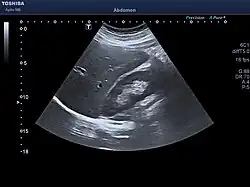

The diagnosis of liver disease is made by liver function tests, groups of blood tests, that can readily show the extent of liver damage. If infection is suspected, then other serological tests will be carried out. A physical examination of the liver can only reveal its size and any tenderness, and some form of imaging such as an ultrasound or CT scan may also be needed.

Sometimes a liver biopsy will be necessary, and a tissue sample is taken through a needle inserted into the skin just below the rib cage. This procedure may be helped by a sonographer providing ultrasound guidance to an interventional radiologist.[73]

-

Axial CT image showing anomalous hepatic veins coursing on the liver's subcapsular anterior surface[74] -

Maximum intensity projection (MIP) CT image as viewed anteriorly showing the anomalous hepatic veins coursing on the anterior surface of the liver -

Lateral MIP view in the same patient as previous image -

A CT scan in which the liver and portal vein are shown